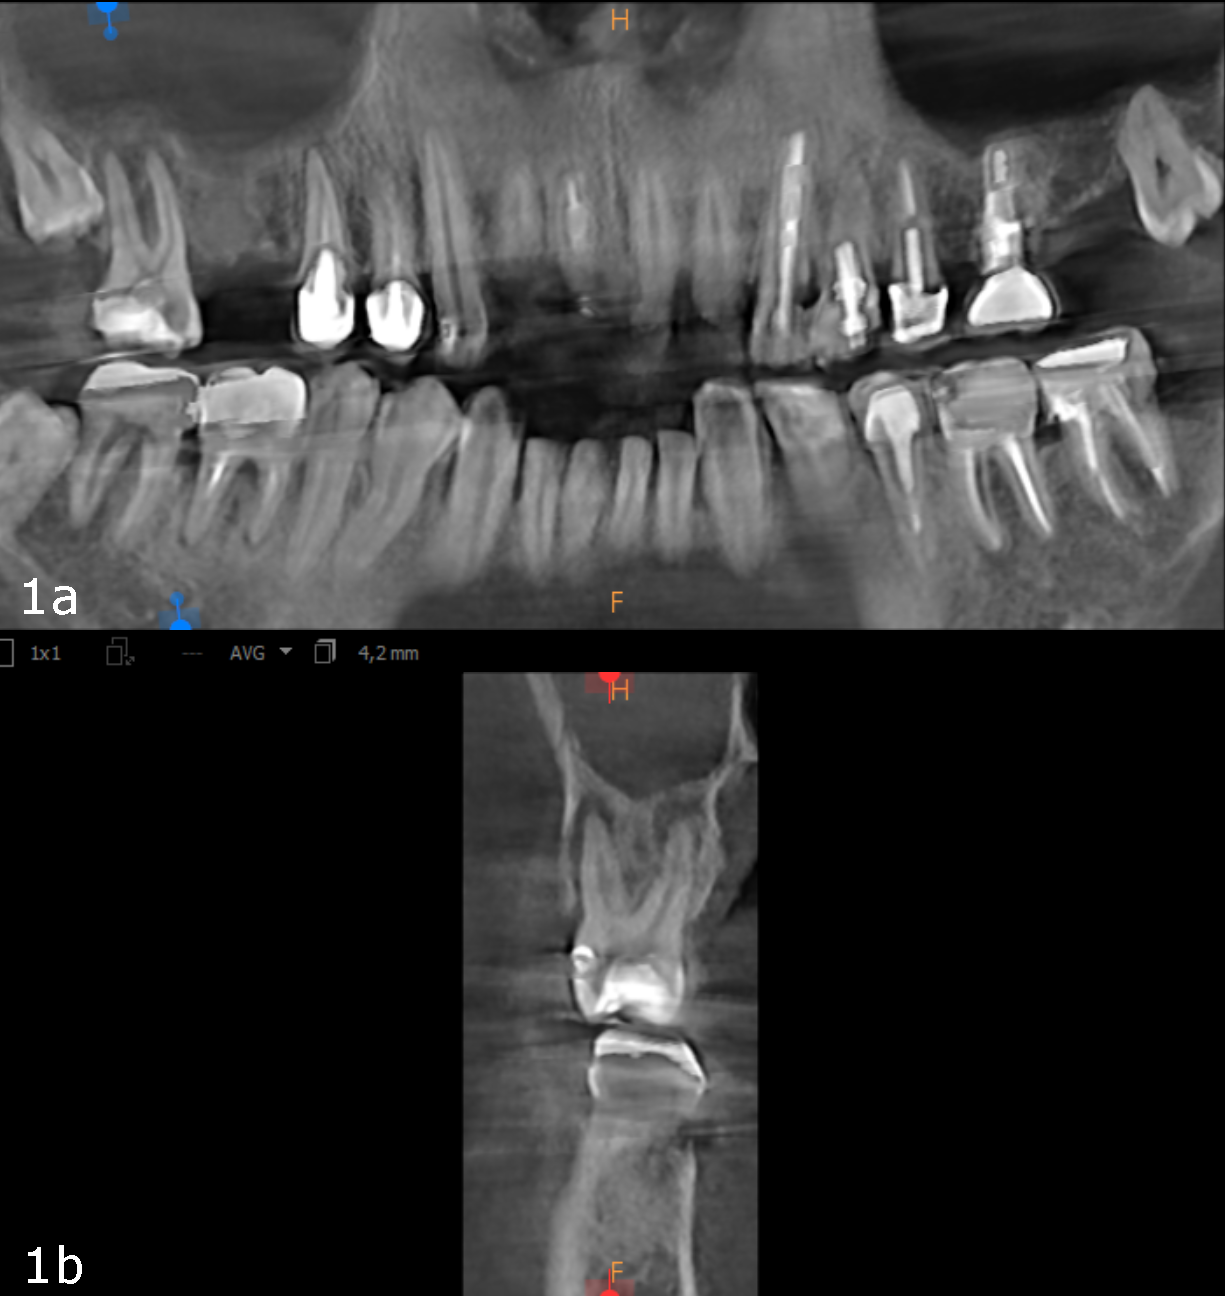

Figs. 1a & b: Initial small-volume CBCT scan, panoramic view (a) and cross-section of tooth #17 (b).

The 61-year-old male patient wanted to have his missing maxillary right teeth replaced with implants. After examination by an implantologist, he was referred to our dental office for further dental treatment because of the findings of a small-volume CBCT scan taken: advanced inflammation and bone loss were visible in the periodontal tissue of the maxillary right second molar and severe maxillary sinusitis was observed (Figs. 1a & b).